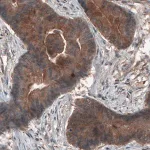

Prestige Antibodies® 라인의 CL3771 클론 단일클론 항체로, 인간 SLCO1B3 단백질을 인식합니다. 정제된 IgG1 형태의 1차 항체이며, 면역조직화학에 적합합니다. −20°C에서 보관하며, 습한 얼음 상태로 배송됩니다.

Prestige Antibodies® Powered by Atlas Antibodies, clone CL3771.

| Technique(s) | Immunohistochemistry (1:500–1:10000) |